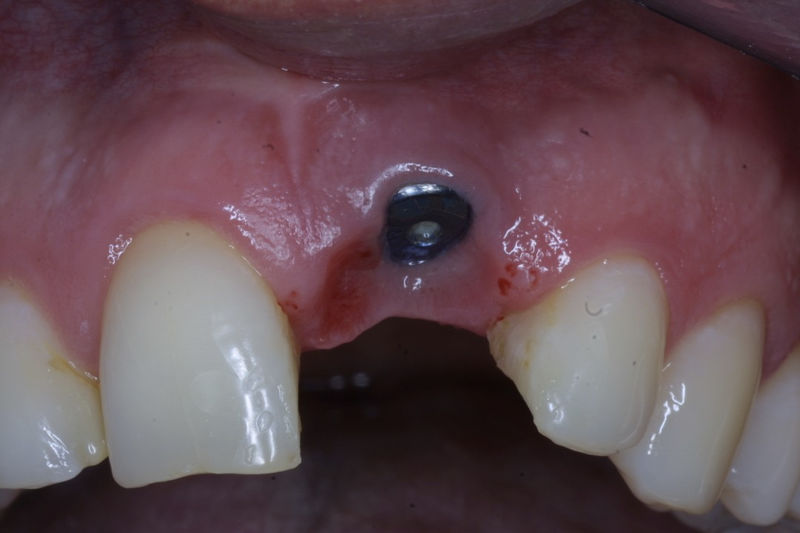

Son estructuras de titanio las cuales se colocan en el hueso y se utilizan para soportar coronas, prótesis fijas, removibles y totales. La colocación de los implantes se hacen previo análisis tomográfico.

Implante fracasado, extracción, carillas, coronas y prótesis fija.